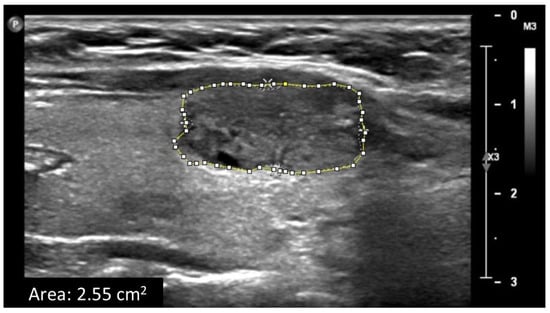

Artificial intelligence is emerging as a powerful new tool for tissue characterization from radiological images. Hence, its application in the diagnosis of cancer diseases is opening up new avenues that could broaden the spectrum of cancers that can be targeted earlier for therapy. From ultrasound to the most sophisticated MRI machines, these advances in imaging are driving changes that could revolutionize the way radiology is perceived.